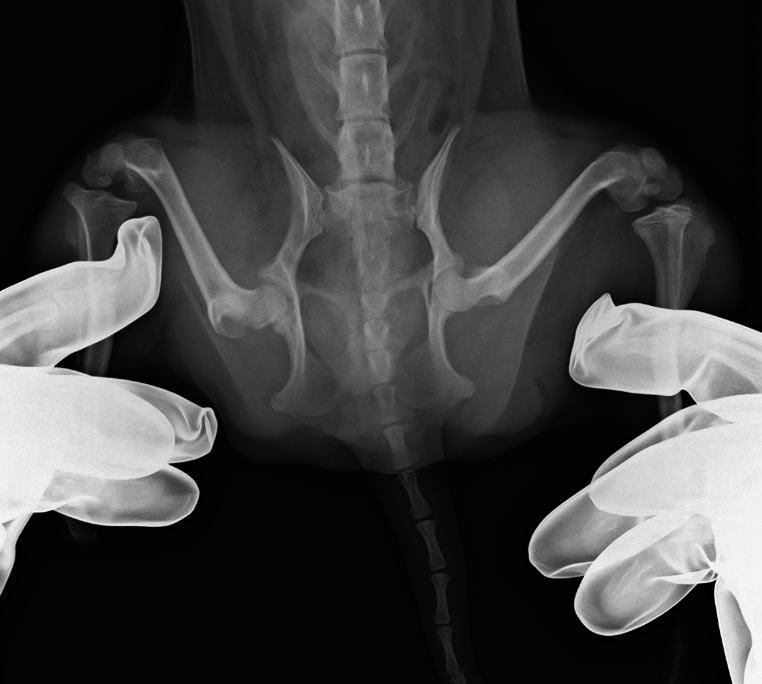

犬

整形外科

大腿骨頭壊死

大腿骨頭壊死とは?

大腿骨頭への血流不全により壊死、変形する病気で、主に若齢の小型犬に多い

症例紹介

犬種

年齢

9ヶ月齢

体重

2.4kg

性別

雄・雌(去勢済/避妊済)

来院のきっかけ

1ヶ月前より右後肢破行・挙上

所見

右後肢大腿骨頭切除

before